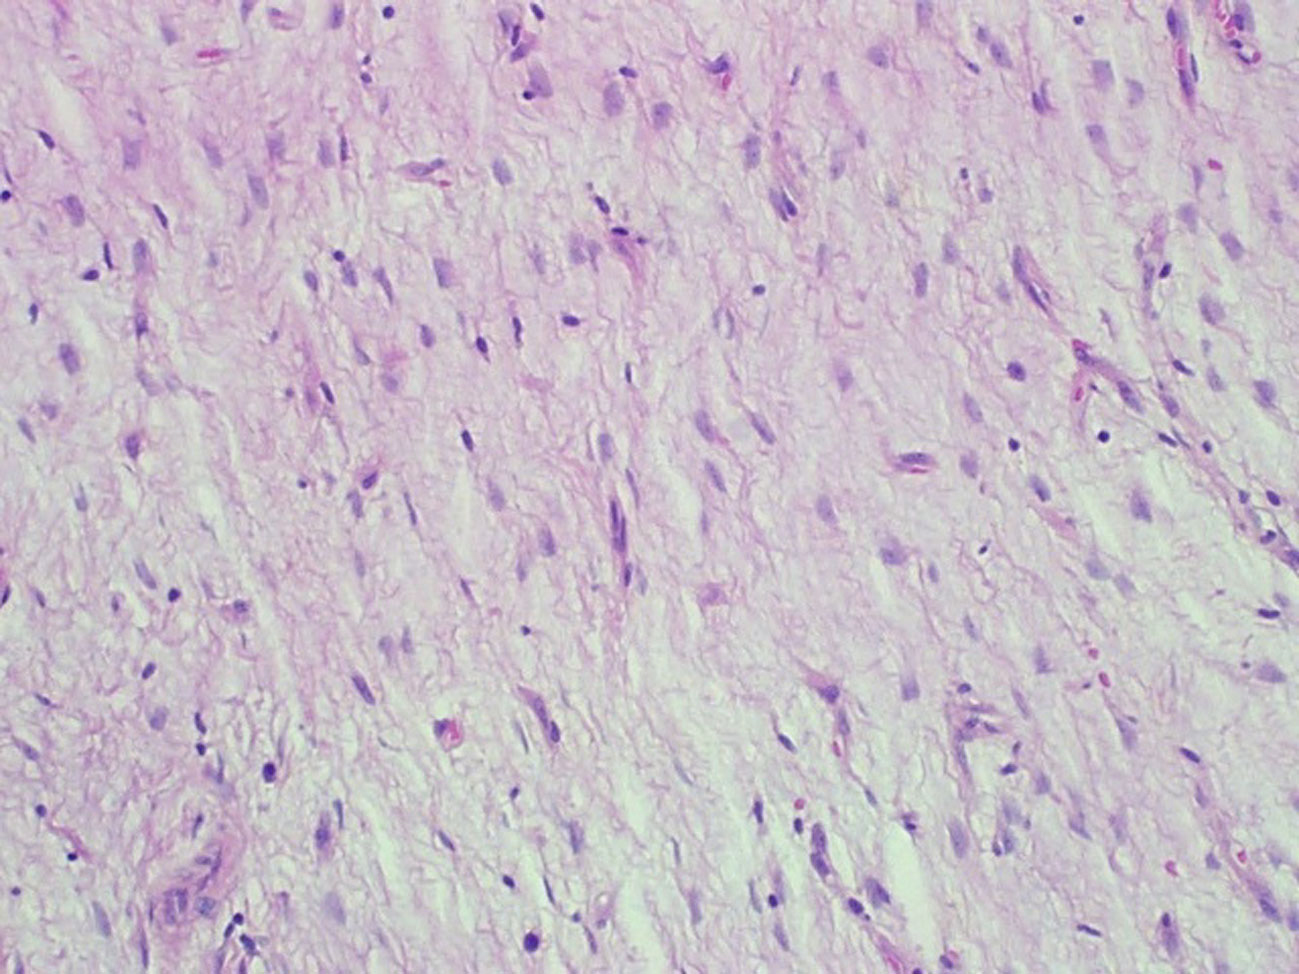

The specimen consisted of a mass weighing 22.8 grams and measuring 6 x 5 x 4.5 cm. The well-defined nodule itself measured 3.5 x 1.8 x 1.5 cm and was found to be gray/white in color with gelatinous consistency on gross examination (Fig. 2). Microscopically the specimen was composed of bland looking spindle shaped cells in a myxoid background and with lymphoid aggregates (Fig. 3, 4). Surgical margins were negative, and the diagnosis of inflammatory myofibroblastic tumor was made.

![]() Click for large image | Figure 3. Hematoxylin and eosin staining (x 200). Loosely arranged spindle shaped fibroblasts devoid of nuclear pleomorphism and atypical mitotic figures with blood vessels in the background. |

![]() Click for large image | Figure 4. Hematoxylin and eosin staining (x 400). Plasma cells admixed with the spindle cells in a loose fibromyxoid background. |

Histologically IMT is characterized by spindle-shaped cells that are mixed with a chronic inflammatory component consisting of plasma cells, lymphocytes, and occasionally histiocytes. Coffin et al. have described three histologic patterns: a myxoid and vascular pattern with inflammatory infiltrate, compact spindle cells proliferation, and hypocellular fibrous pattern [1]. Immunohistochemical studies support the myofibroblastic nature with consistent expression of vimentin and smooth muscle actin with variable positivity for HHF-35, cytokeratins, and CD68. Electron microscopy reveals spinal cells with abundant endoplasmic reticulum, pinocytotic vesicles, basal lamina, and extracellular collagen [1].